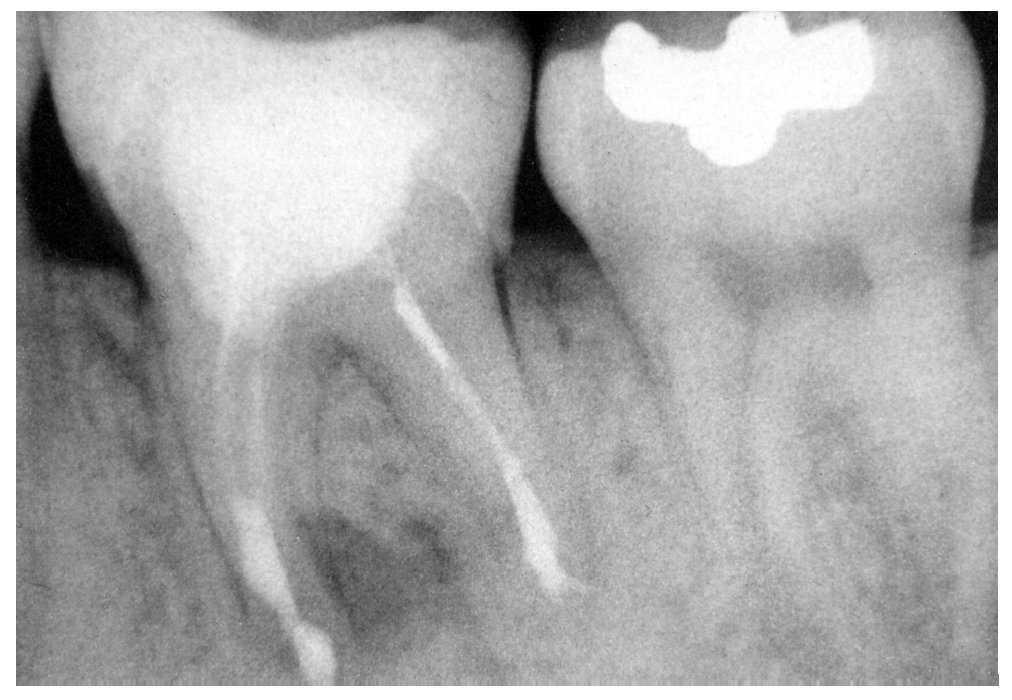

Figura 2a. Cuatro años después de una apicectomía se observa una imagen radiolúcida periapical posterior a un tratamiento endodóntico insuficiente del diente 46.

Figura 2b. Se observa una tendencia clara a la curación seis meses después de la reendodoncia ortógrada del diente 46.